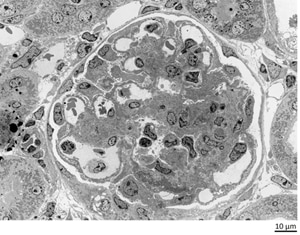

在病理组织解析方面,也有肾脏疾病的案例,由于肾脏结构复杂且症状隐匿,肾病早期很难显现主观症状。加上肾病种类繁多,难于判别等原因,被视为“难确诊”的疾病。

一般情况下,通过透射电镜(TEM)对肾小球基底膜及沉积物的纳米级结构表征,可实现病理诊断的精准判别。

使用TEM观察大鼠肾脏实例